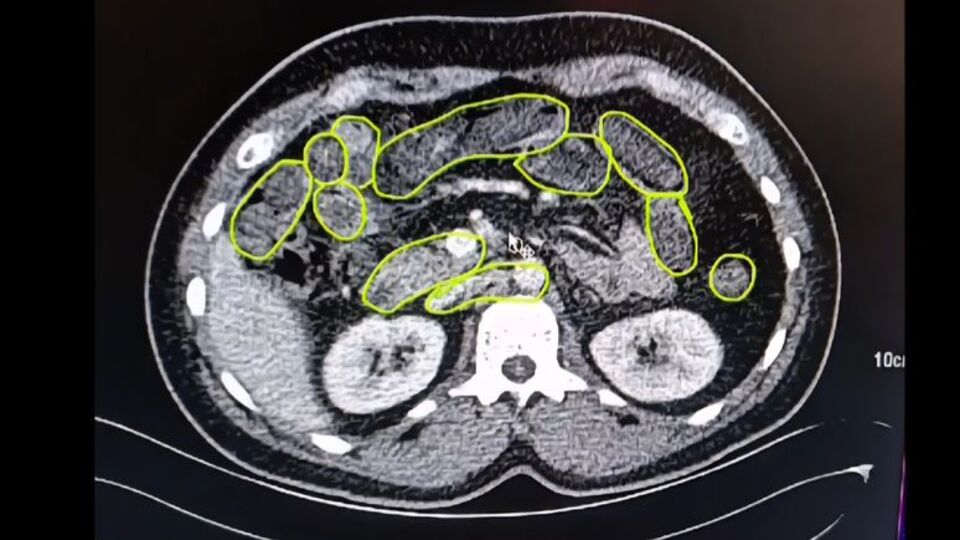

Şüphelilerin Kayseri Şehir Hastanesinde iç beden muayenesine alınırken, mide ve bağırsaklarında da çok miktarda kapsül şeklinde uyuşturucu olduğu değerlendirilen yabancı maddeler tespit edildi.